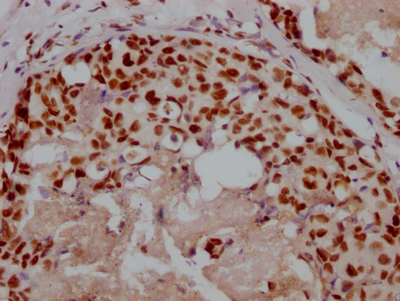

IHC image of CSB-PA896505DSR2HU diluted at 1:50 and staining in paraffin-embedded human kidney tissue performed on a Leica BondTM system. After dewaxing and hydration, antigen retrieval was mediated by high pressure in a citrate buffer (pH 6.0). Section was blocked with 10% normal goat serum 30min at RT. Then primary antibody (1% BSA) was incubated at 4°C overnight. The primary is detected by a Goat anti-rabbit polymer IgG labeled by HRP and visualized using 0.05% DAB. Secondary antibody only control: uses 1% BSA instead of primary antibody